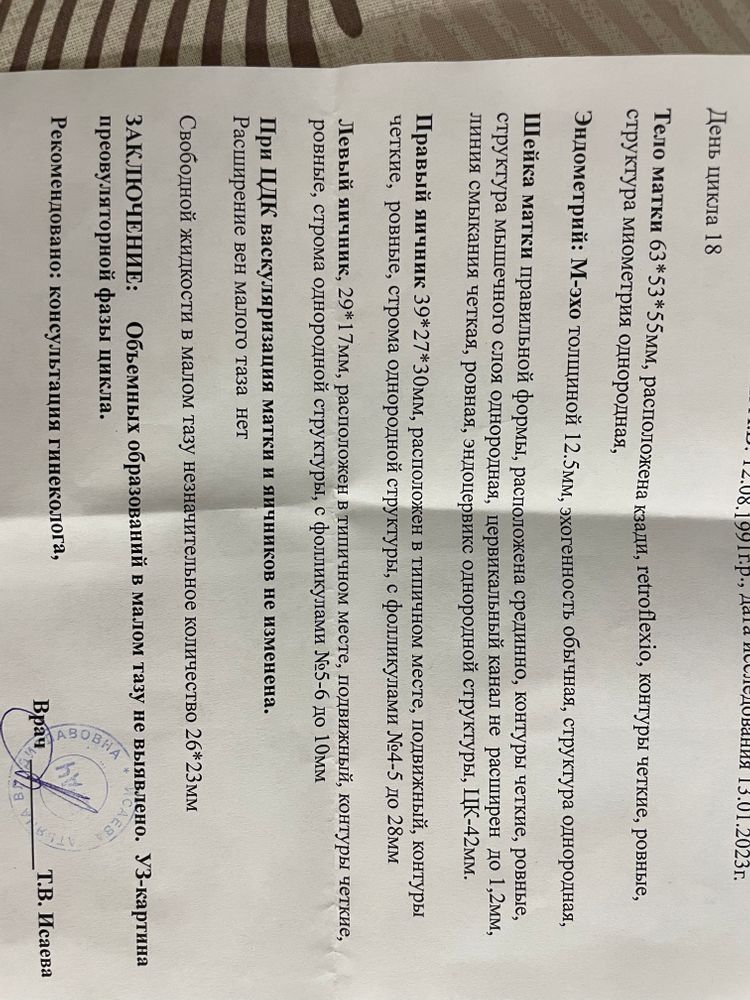

Не знаю, что там было в Рождество) но точно не киста🤷♀️😄 и не овуляция! Вы были правы! Спасибо тем, кто со мной спорил☺️ и говорил, что овуляции ещё не было😄

ОВУЛЯЦИЯ СЕЙЧАС! СЕГОДНЯ И ЗАВТРА!

Я счастлива!😄 И да, всё тот же правый яичник❤️